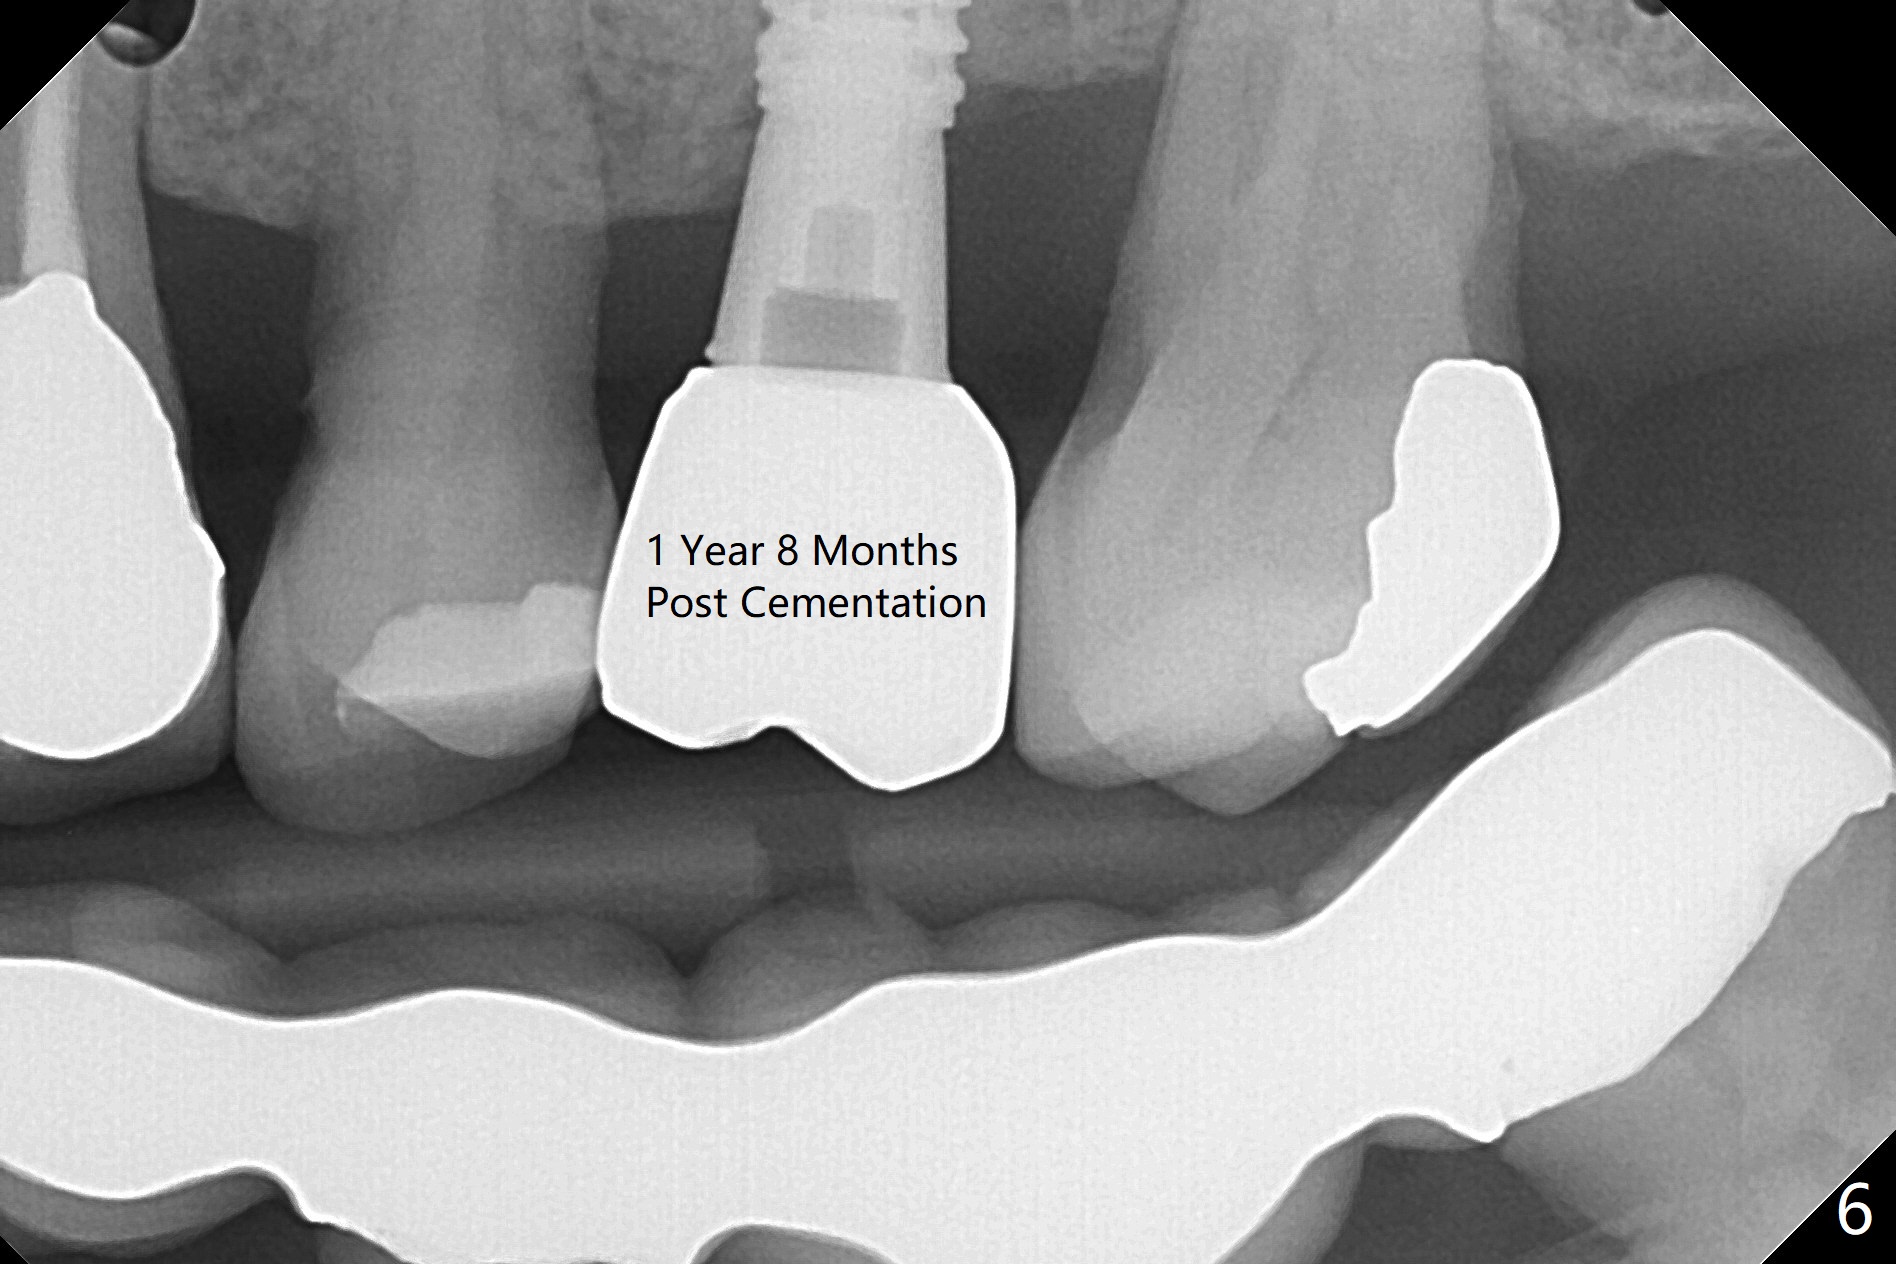

While the implant is being osteointegrated, the edentulous space increases from 5.5 mm to 7.39 mm using the distal anchor implant in 3 months (Fig.5).  The patient is able to masticate normally 1 year 8 months post cementation (Fig.6).  The mesiodistal width of the crown is 7.9 mm.  There is no bone loss 23 months post cementation (Fig.7).